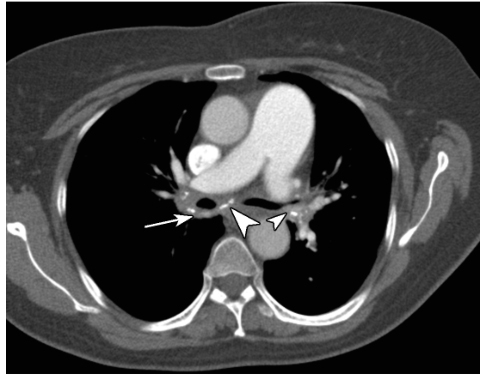

图1 慢性纵隔炎

患者,女,59岁,胸部CT增强扫描纵隔窗示纵隔隆突下及双肺门区多发软组织密度影(白箭),内伴多发斑点状钙化(白箭头),病变包绕双侧支气管及肺动脉;肺动脉主干增宽,提示肺动脉高压。